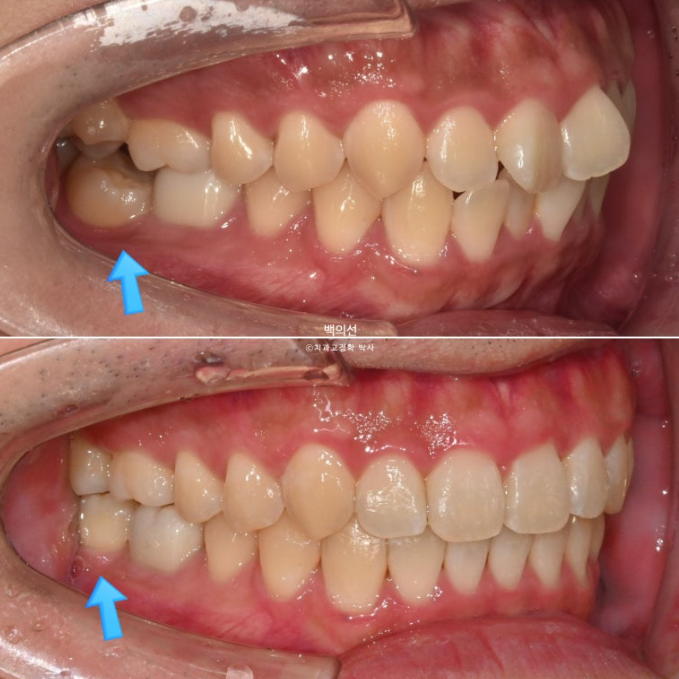

파란 화살표 치아끼리 엇갈려 물리는 가위교합으로 교합이 안되는 상태입니다.

특히 아래 두번째 큰어금니는 쓰러져 있습니다.

환자분은 투명교정을 원했기 때문에 투명교정장치 제작 전 쓰러진 어금니와 가위교합을 먼저 개선해놓고, 나머지 앞니 삐뚠 부분은 인비절라인 라이트로 해결하기로 했습니다.

치료시작 3개월차 사진입니다. 먼저 4군데 사랑니를 다 뽑았습니다.

쓰러진 큰어금니와 그 앞의 큰어금니에 총 2개의 브라켓을 붙이고 철사를 넣어 치아를 세웠습니다.

그 사이 입천장에는 가위교합 개선을 위해 교정용 나사 미니스크류를 심고 바깥으로 뻗쳐있던 큰어금니를 제 위치 시켰습니다.

치료시작 6개월차, 쓰러진 큰어금니가 서고 가위교합이 해소가 되었습니다.

24.01~24.07